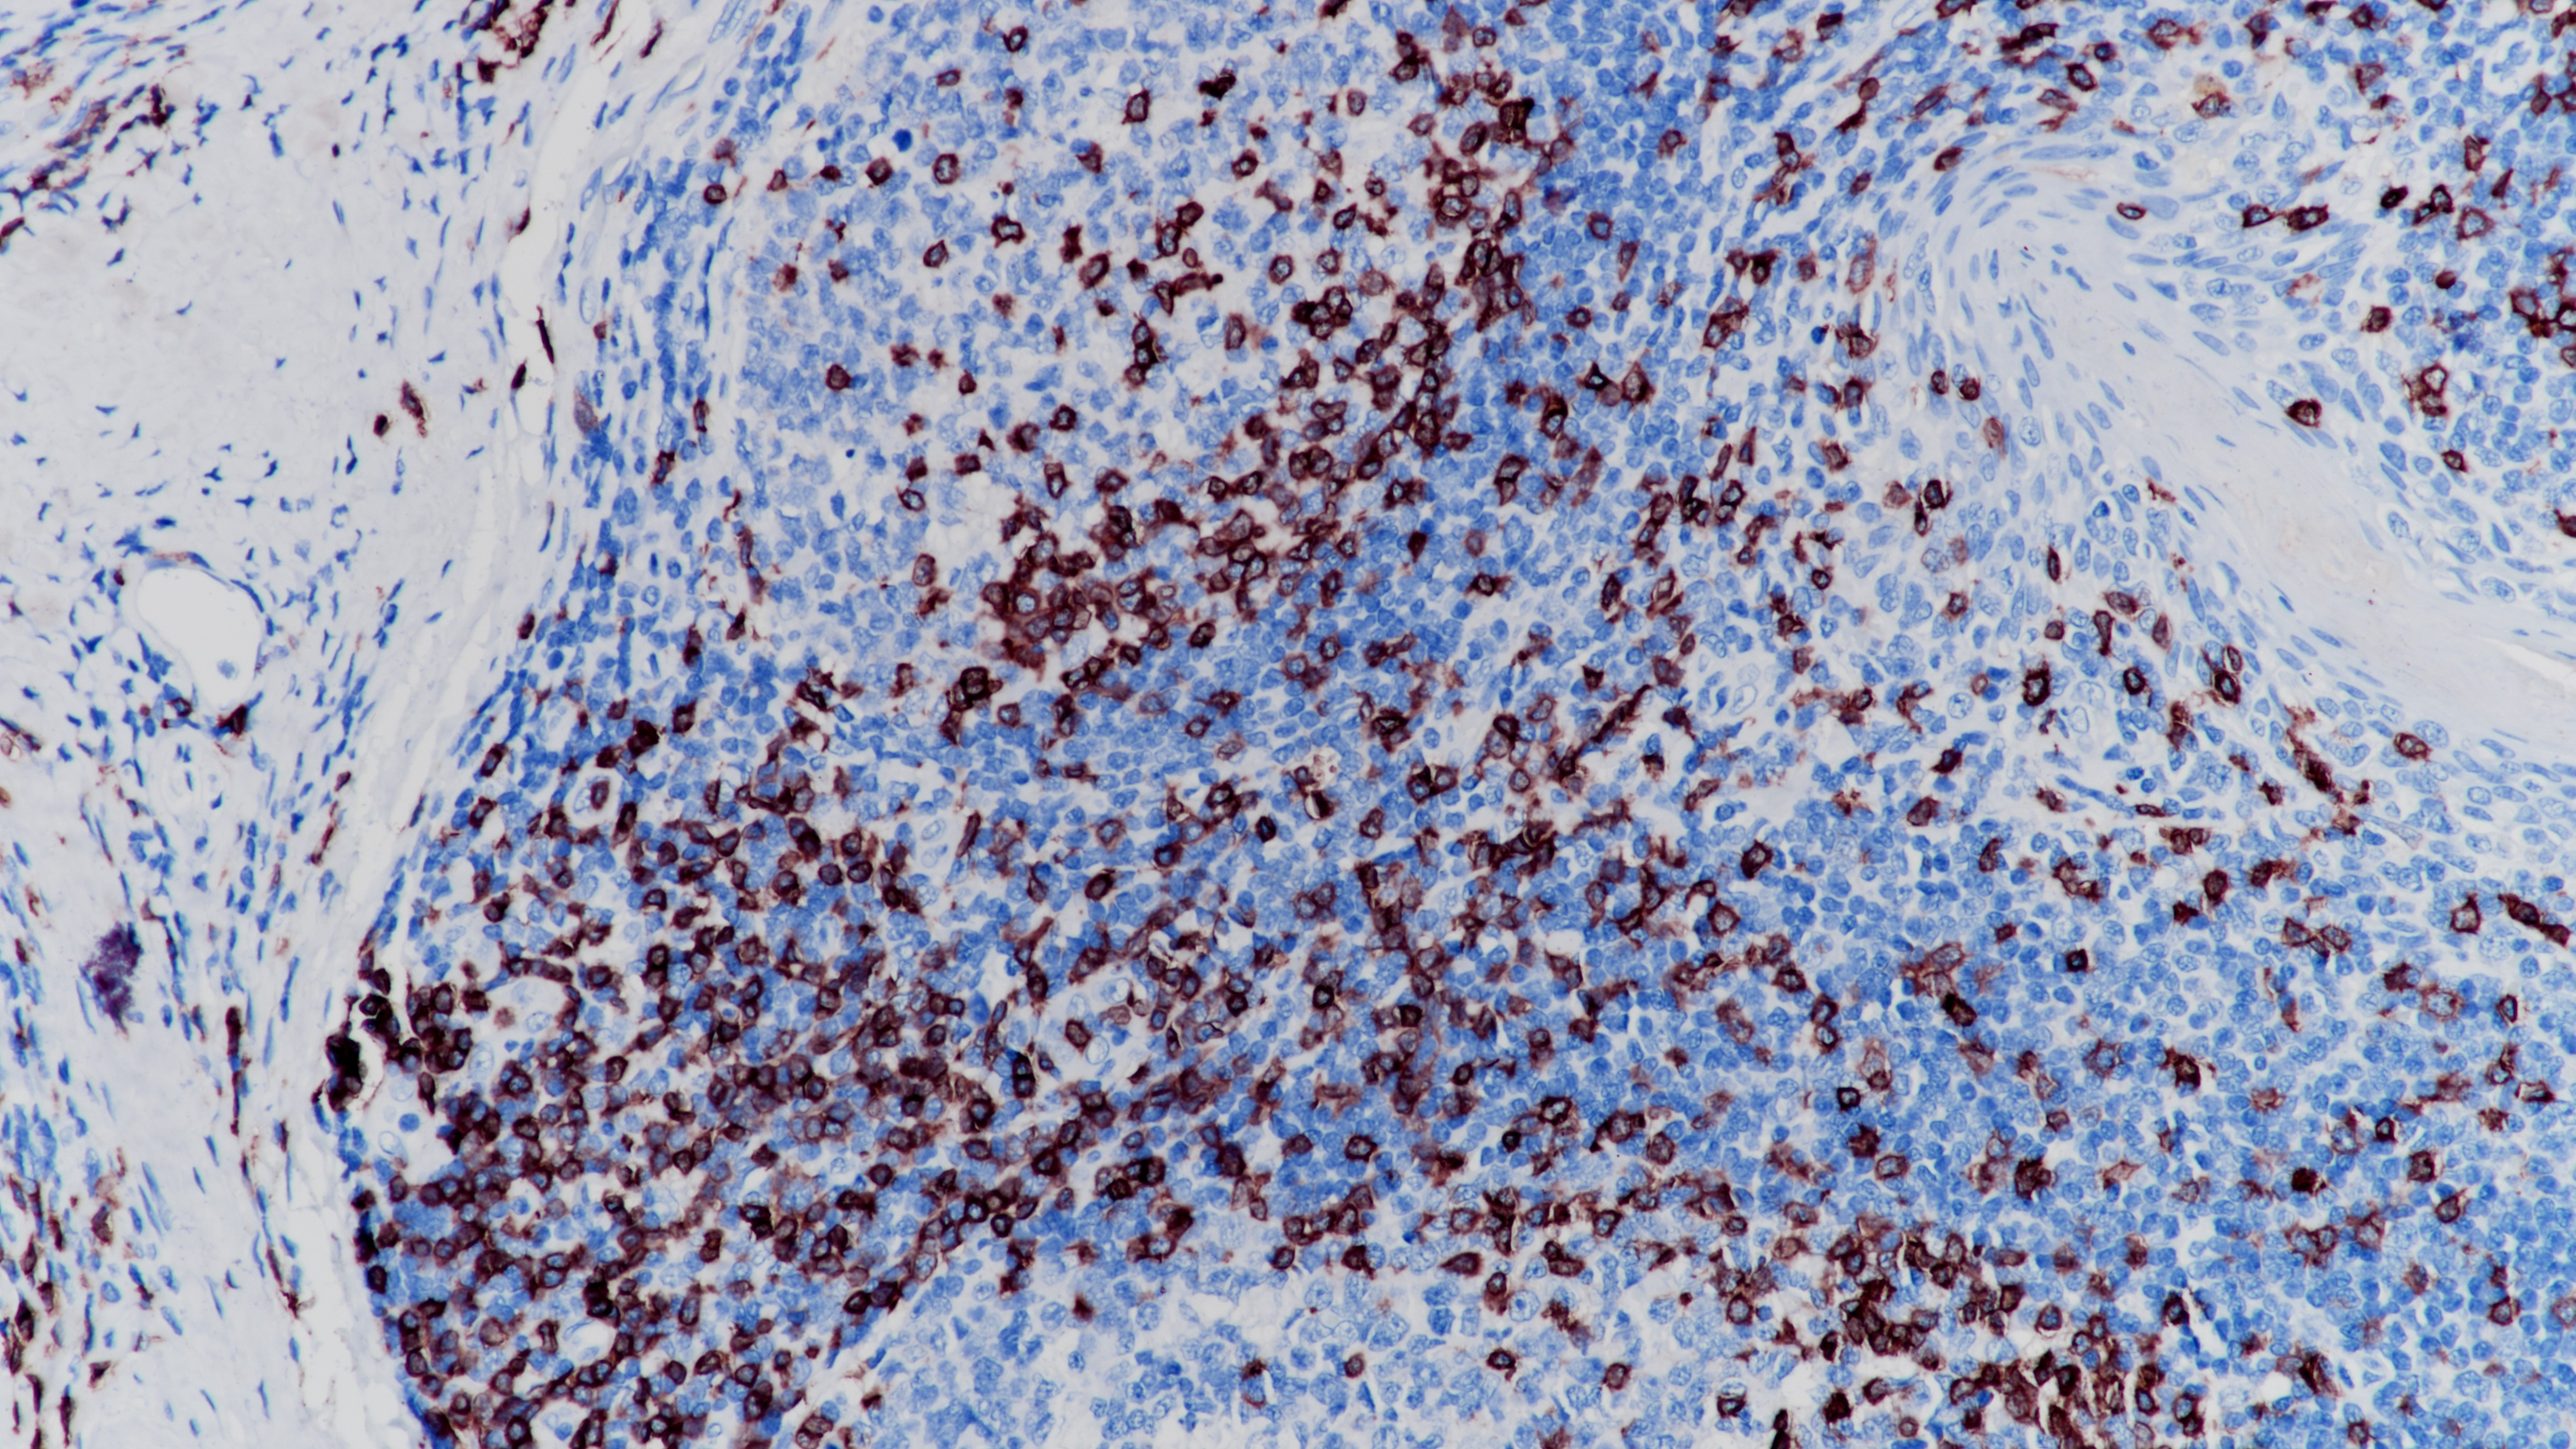

1. Campana D, et al. The cytoplasmic expression of CD3 antigens in normal and malignant cells of the T lymphoid lineage. J Immunol. 1987 Jan; 138(2):648-55.

2. Steward M, et al. Production and characterization of a new monoclonal antibody effective in recognizing the CD3 T-cell associated antigen in formalin-fixed embedded tissue. Histopathology. 1997 Jan; 30(1):16-22.